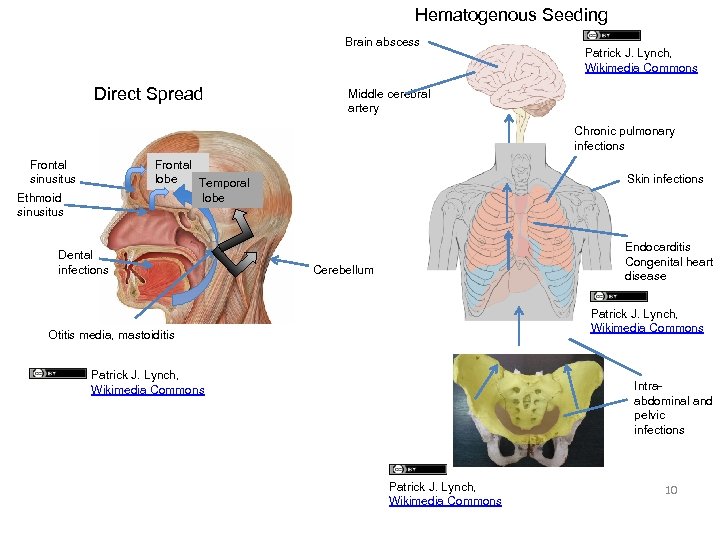

Hematogenous Seeding Brain abscess Direct Spread Patrick J. Lynch, Wikimedia Commons Middle cerebral artery Chronic pulmonary infections Frontal sinusitus Frontal lobe Temporal lobe Ethmoid sinusitus Dental infections Skin infections Endocarditis Congenital heart disease Cerebellum Patrick J. Lynch, Wikimedia Commons Otitis media, mastoiditis Patrick J. Lynch, Wikimedia Commons Intraabdominal and pelvic infections Patrick J. Lynch, Wikimedia Commons 10